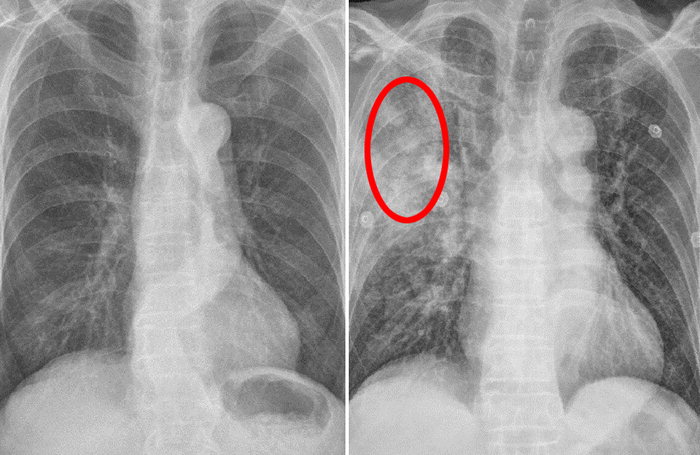

이러한 폐암의 원인으로 인해 폐암으로 진단되기 전에 폐암 초기증상을 조기에 발견하면 다른 장기로의 전이나 진행성 폐암으로의 진행을 어느 정도 지연시키거나 적절하게 치료할 수 있지만 일반적으로 폐암의 초기 단계는 특별한 징후나 증상이 없으므로 조기에 발견하는 경우는 극히 드뭅니다.

폐암의 초기증상 중에 흉통이 있습니다. 폐암 환자의 약 1/3이 흉통을 호소합니다. 흉통의 원인은 폐 가장자리에 종양이 형성되어 암세포를 생성하고 흉벽과 흉막에 침착되어 통증을 유발하는 것입니다.

흉통의 원인은 여러 가지가 있을 수 있지만, 오늘날 우리가 다루고 있는 폐암으로 인한 흉통은 경미한 통증보다는 지속적인 따끔거림과 둔한 통증을 동반한다는 점에 유의하시기 바랍니다. 또한 암은 흉막이나 흉벽 대신 갈비뼈로 퍼져 통증을 유발할 수 있습니다. 종양은 주변 조직 세포를 자극할 수 있으므로 계속해서 통증을 유발하는 경우 의사의 진찰을 받는 것이 좋습니다.